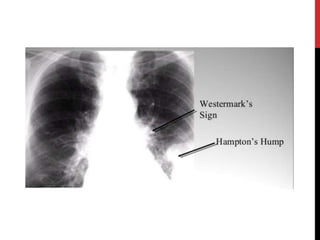

1- X-ray:

• Fewer vascular markings (pulmonary oligaemia)

• Hampton’s hump sign

Wedge-shaped infarct

• Westmark’s sign

Hyperlucency in the lung region supplied by the affected

artery

INVESTIGATIONS Imaging : 1- X-ray: •Fewer vascular markings (pulmonary oligaemia) • Hampton’s hump sign Wedge-shaped infarct • Westmark’s sign Hyperlucency in the lung region supplied by the affected artery